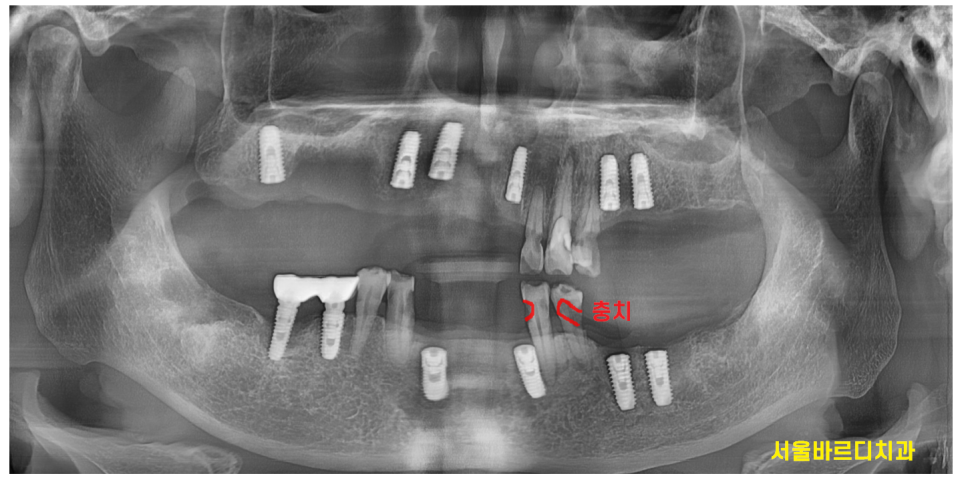

천호동 치과 치료의 끝나고 촬영한 X RAY입니다.

CT대로 분석하고 임플란트를 하다보니

처음 계획대로 치료가 완료되었습니다.

이제 위 아래 치아끼리 맞물리니

빠른 시기로 충치가 많이 먹은 치아들을 치료하는 것으로

2차 계획을 세워야겠습니다.